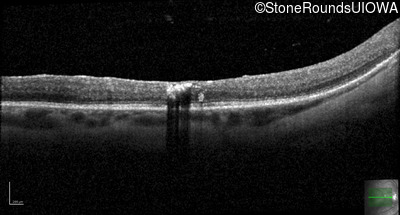

Age at visit: 49 years

Age at visit: 50 years